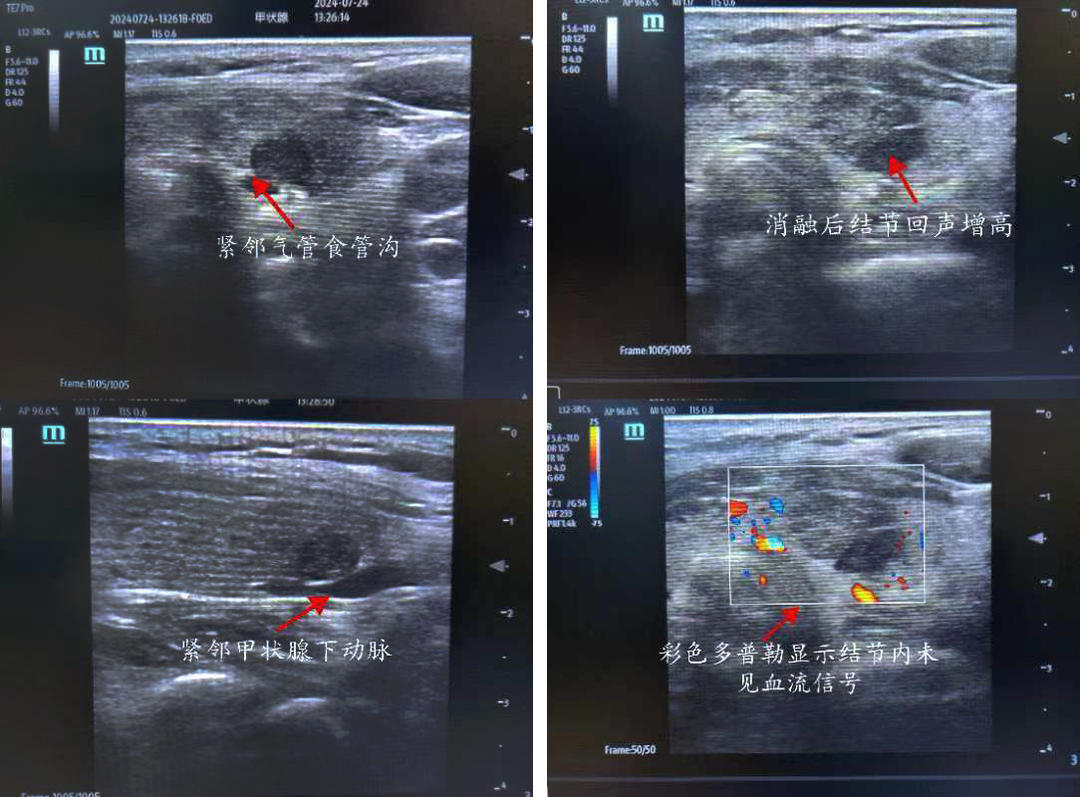

患者,女,50岁,甲状腺彩超示:甲状腺左侧叶下极探及一约0.8*0.3cm低回声结节,界尚清,形态不规则,内回声不均质,内似可见点状强回声,周边及其内可见血流信号 TI-RADS 4a级。入院后行甲状腺左侧叶结节细针穿刺细胞学检查+BRAF基因检测,结果示:考虑为滤泡上皮细胞非典型病变,BRAFV600E基因检测未见突变。但患者左侧叶4a结节位于腺体背侧,紧邻气管食管沟,与左侧喉返神经走行位置相近,患者自觉复查随访心理压力大,强烈要求积极处理此结节。但因传统手术切除治疗创伤较大,美观性较差,且术后可能需终身服药,患者不愿接受手术切除。

俞景奎主任医师、孙守毅副主任医师及诊疗组详细分析讨论后,决定为患者行超声引导下甲状腺左叶结节微波消融术。对于该患者而言,行微波消融治疗有两大难点,一是患者左叶结节位于腺体背侧,紧邻左侧喉返神经,消融治疗易损伤喉返神经致声音嘶哑;二是彩超下见患者左叶结节背侧紧贴甲状腺下动脉,易出现血管损伤出血情况。在李峰主任和俞景奎主任医师支持指导下,孙守毅副主任医师及马凯丽主治医师为患者制定详细手术方案,术中在结节与周围重要组织结构之间建立隔离带,形成安全隔离区域,力争将患者手术风险降到最低。最终,患者顺利完成手术,且术后血管和喉返神经均无损伤,患者声音无变化, 顺利康复出院,对治疗效果非常满意。